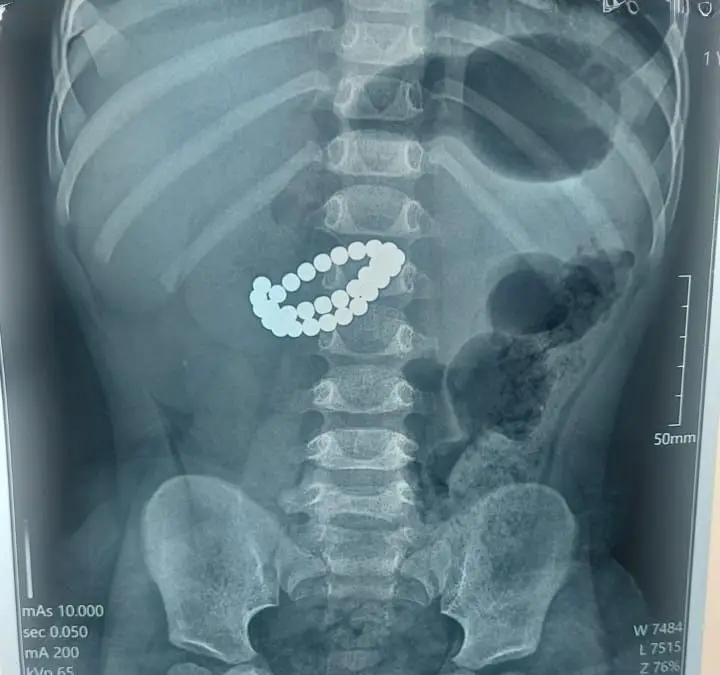

В Алматы медики провели экстренную операцию, чтобы спасти жизнь 1,9-летнему ребенку, который проглотил 31 магнит. Малыш поступил в Центр детской неотложной медицинской помощи в крайне тяжелом состоянии, где врачи диагностировали у него множественные перфорации тонкой кишки и диффузный каловый перитонит. Единственным способом спасти ребенка стало срочное хирургическое вмешательство.

Хирурги выполнили срединную лапаротомию, которая позволила провести ревизию органов брюшной полости. В ходе операции были извлечены все магниты, а также ушиты перфорации в тонкой кишке. Кроме того, врачи провели санацию и дренирование брюшной полости, а также трансанальную интубацию кишечника.

Как отметил хирург Аскар Ризванов, опасность магнитов заключается в их способности притягиваться друг к другу внутри кишечника. Это приводит к зажиму стенок кишки, нарушению кровообращения и некрозу тканей, что может вызвать перитонит всего за несколько часов. Врачи предостерегают родителей: даже один проглоченный магнит — это серьезная угроза для жизни ребенка.